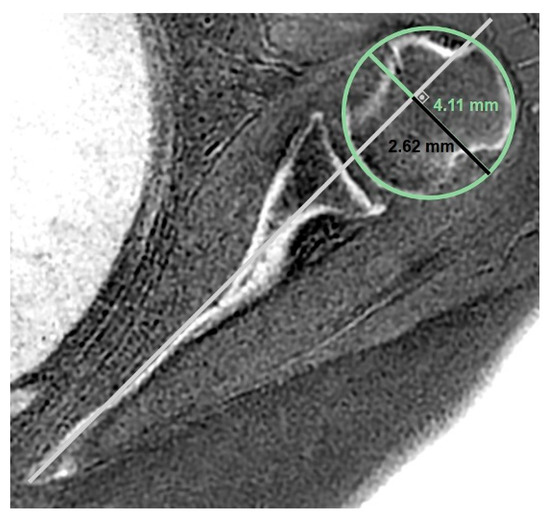

Background/Objectives: Evaluating glenoid changes in rotator cuff tear arthropathy (RCTA) is crucial for preoperative planning. MRI with zero echo time (ZTE) sequence, which produces CT-like images, allows for the assessment of osseous morphology as well as factors contributing to pseudoparesis in RCTA patients. [...] Read more.

Background/Objectives: Evaluating glenoid changes in rotator cuff tear arthropathy (RCTA) is crucial for preoperative planning. MRI with zero echo time (ZTE) sequence, which produces CT-like images, allows for the assessment of osseous morphology as well as factors contributing to pseudoparesis in RCTA patients. Methods: In this retrospective study, using 3T MRI, glenoid version, glenoid vault depth, humeral subluxation index, humeral head medialization, critical shoulder angle, glenoid best-fit circle width, glenoid best-fit circle bone loss ratio (GBLR), and anterior, central, and posterior glenoid bone loss were measured on reformatted 3D ZTE images in 43 shoulders independently by three observers. The same measurements were repeated by one observer after 10 days. Muscle cross-sectional areas were measured. Patients’ active ROMs, American Shoulder and Elbow Surgeons (ASES), and Constant–Murley scores were recorded. Patients unable to perform 90° forward elevation were classified as the pseudoparesis group. Results: Interobserver agreements were good to excellent, except for glenoid vault depth, anterior bone loss, and GBLR. Intraobserver agreements were good to excellent. The pseudoparesis group showed significantly less subscapularis muscle cross-sectional area (p = 0.006). Moderate correlations were found between subscapularis cross-sectional area and forward elevation, abduction, and internal rotation ([r = 0.471, p = 0.001]; [r = 0.447, p = 0.003]; [r = 0.464, p = 0.002], respectively). Moderate negative correlations were found between anterior glenoid loss and forward elevation (r = −0.411, p = 0.006) and abduction (r = −0.475, p = 0.001). Conclusions: MRI with ZTE sequence demonstrated good reliability for assessing osseous morphology in shoulders with RCTA. Glenoid anterior bone loss and loss of subscapularis muscle are both associated with pseudoparesis. Full article

Show Figures

Figure 1